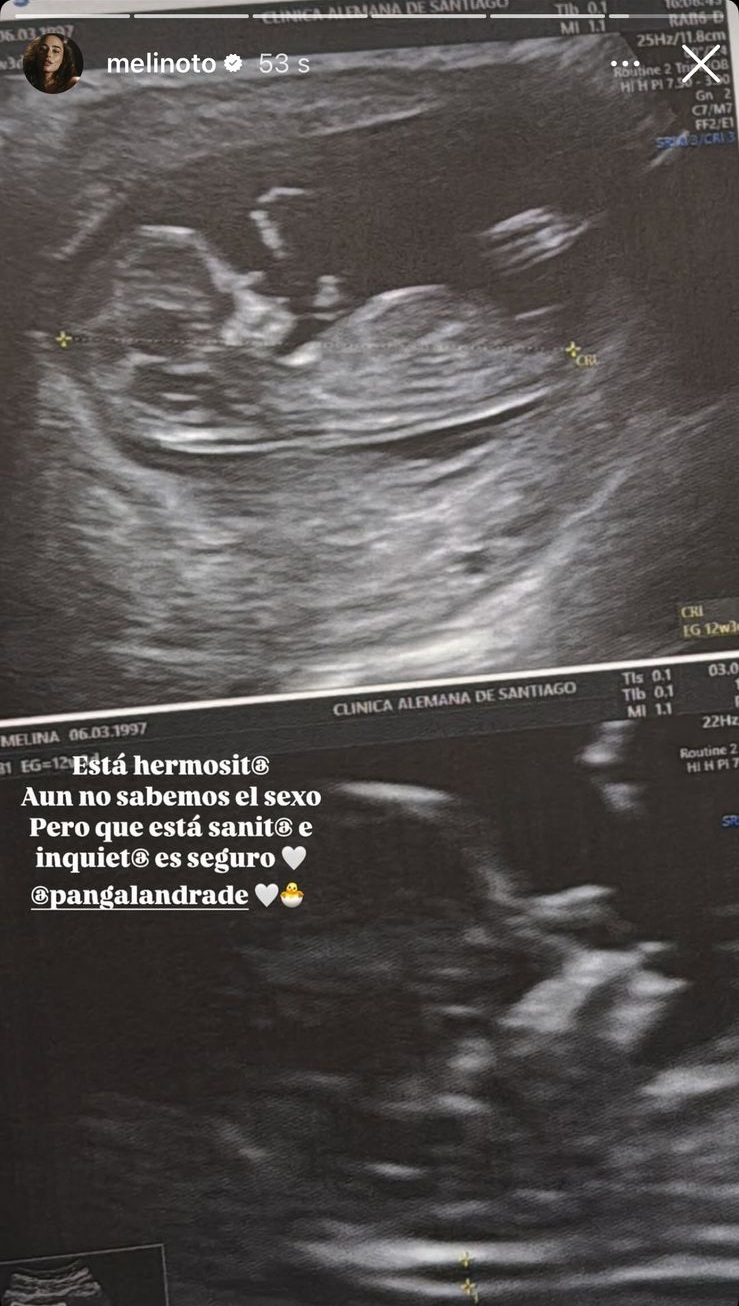

Pangal Andrade y Melina Noto: La foto de la ecografía

Cerca de las 19:00 horas, la joven madre compartió con sus seguidores una foto de la ecografía, adelantando que el bebé no quiso "mostrarse" por lo que el sexo continuará siendo un misterio.

"Está hermosit@. Aún no sabemos el seco, pero que está sanit@ e inquiet@ es seguro", escribió.